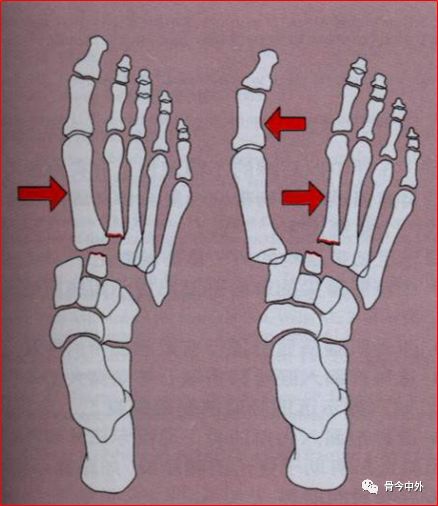

1.Quenu和Kuss分类

• 孤立型:至少一块跖骨而非全部跖骨单向脱位。

• 同侧型:所有跖骨一致向内或更经常是一致向外半脱位或脱位。

• 分离型:跖骨向不同方向或在一个以上平面分离。

2.Myserson改良分类A型:包括全部5块跖骨的移位,伴有或不伴有第2跖骨基底骨折。常见移位是外侧或背外侧移位,跖骨作为一个整体移位。这类损伤常称为同侧型。

B型:一个或多个关节仍然保持完整。B1——内侧移位,有时累计楔间或舟楔关节。B2——外侧移位,可累及第一跖楔关节。

B1——内侧移位;B2——外侧移位

C型:属于裂开性损伤,根据裂开程度分为C1部分裂开、C2全部裂开。这类损伤通常是高能量损伤,应特别注意筋膜间室综合征。

C1部分裂开;C2全部裂开